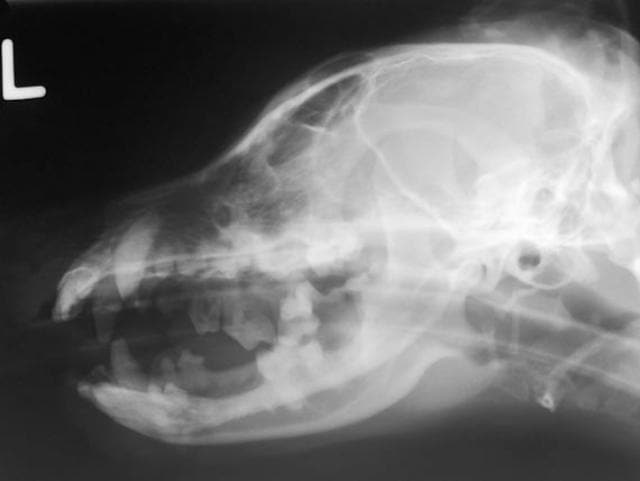

How Veterinarians Diagnose Brain Tumors in Cats

If your veterinarian suspects a brain tumor, they may use a combination of tests to reach an accurate diagnosis, including:

Advanced imaging—To accurately diagnose a brain tumor, an MRI or CT scan of the brain is required, which involves the cat being placed under general anesthesia. An MRI is preferred because it provides more detail.

Biopsy—A CT-guided biopsy, which involves obtaining a small sample of the brain tumor with the aid of CT imaging, may be used to determine the type of tumor.